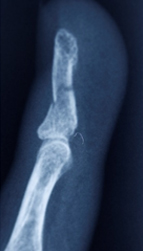

Distal falanks, parmak ucundaki kemiktir. Uygun parmak fonksiyonu ve tırnak büyümesi için sabit bir distal falanks gerekir. Çoğu distal falanks kırığının düzeltilmesi gerekmezken, bazılarının düzeltilmesi gerekir. Bunlar, düzgün bir şekilde birleştirilmesi gereken birçok parça ile oldukça karmaşık olabilir. Kötü bir şekilde düzeltilmiş kırıklar iyi iyileşmez, çok fazla ağrıya neden olur ve işe dönüşü geciktirir.

Eldeki kapalı kırıklar, yerinden oynamışsa veya deformiteye neden oluyorsa, uygun hizaya geri konulmalı ve ele iyi bir fonksiyon kazandırmak için metal teller, vidalar veya plakalarla sabitlenmelidir. Bu, el yaralanmasından birkaç gün sonra, mümkün olan en kısa sürede erken rehabilitasyona izin vermek için en iyi şekilde yapılır.